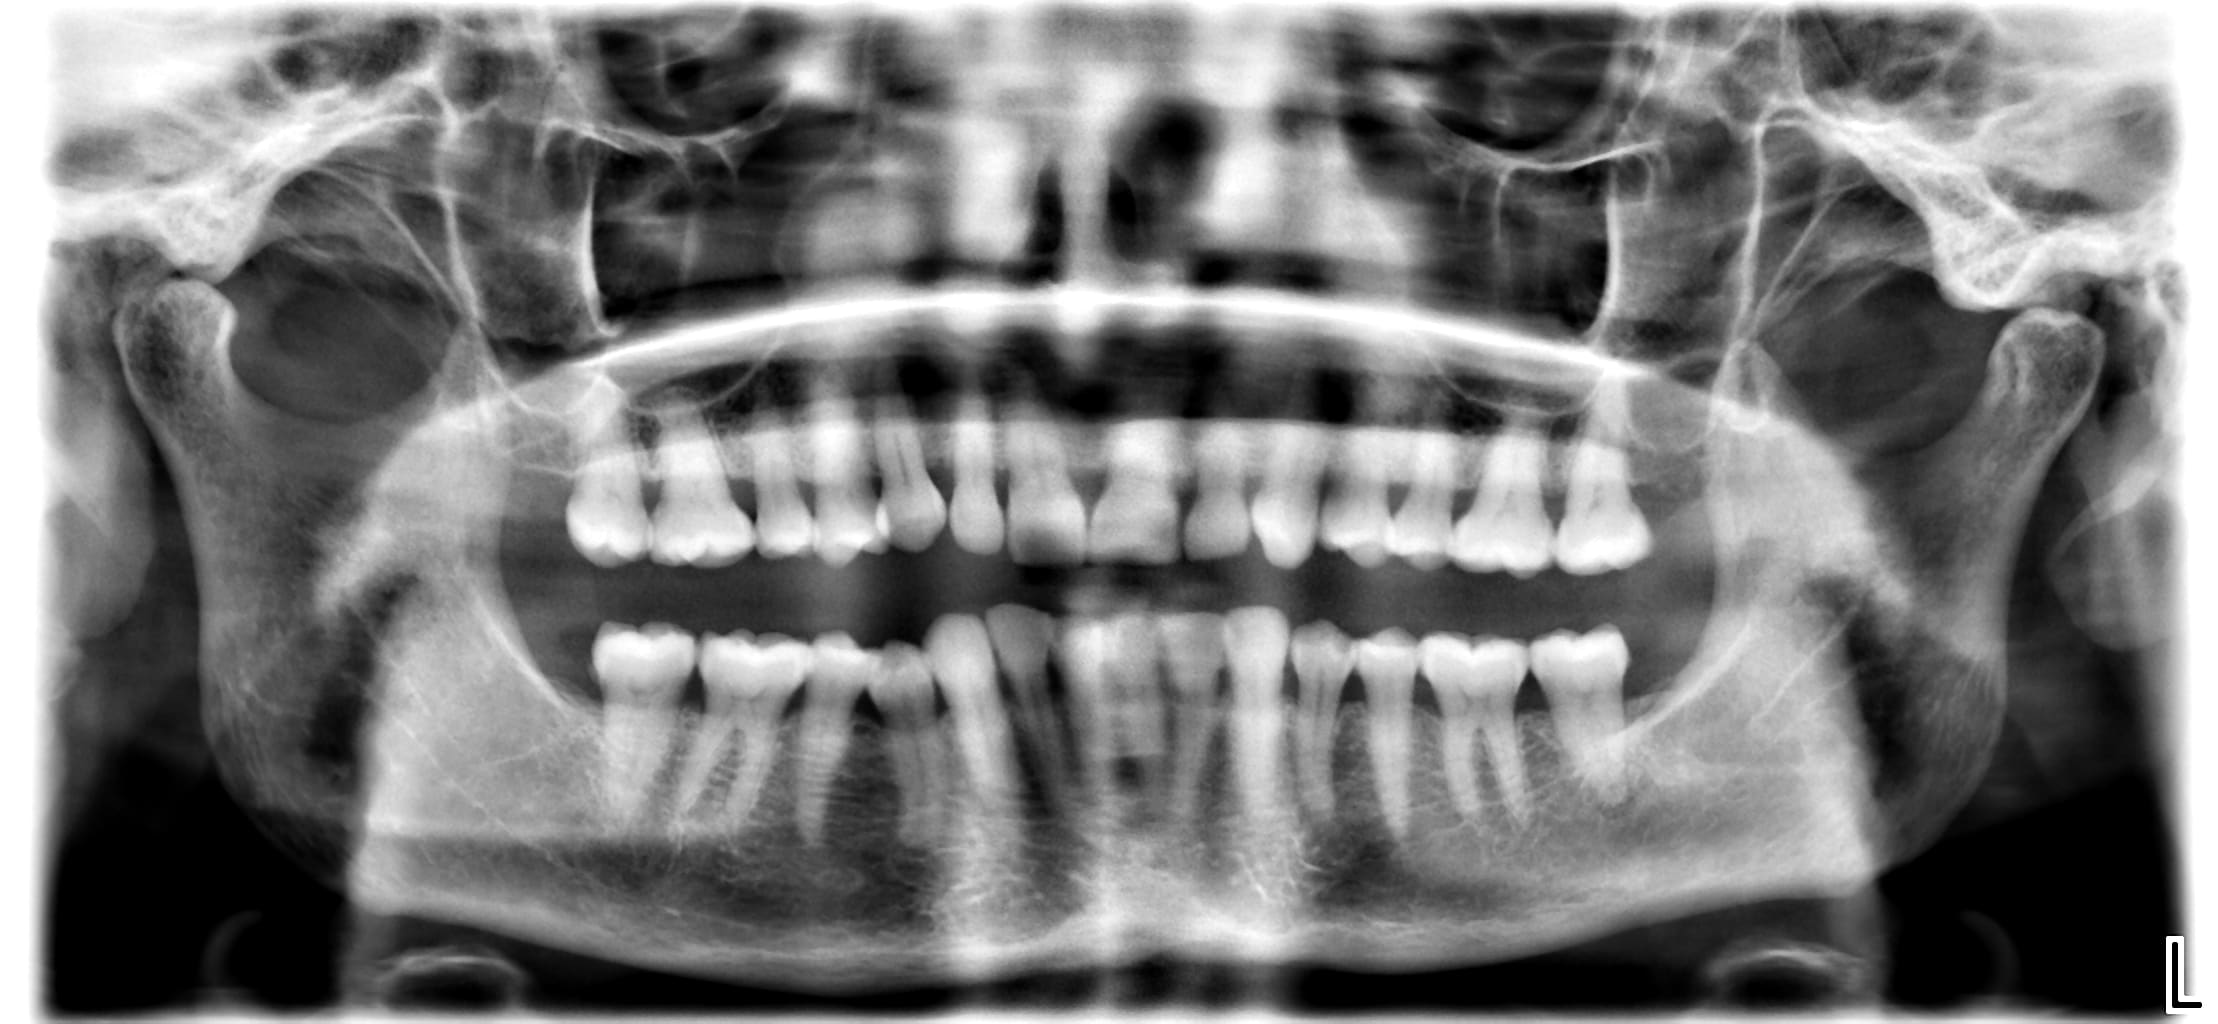

J'aimerais votre avis pour ce cas. Je suis sûre à 99% qu'il faille dévitaliser la 37 suite à pour moi un abcès apical aigu mais je ne trouve pas de réelle cause et j'aimerais savoir si vous aviez une idée.

09/06 : 37 a eu petite gene dernierement a la mastication très léger par moment. Tartre ++ en occlusal de 27 je pense à une sur sollicitation. Elargissement desmodontal sur la radio mais froid positif donc surement traumatique par surocclusion? Si perdure peut etre fracture? A ré évaluer.

07/07 37 : douleur type abcès apical aigu il y a 2 semaines calmées par les ATB. // Scan pour recherche origine fracture, RAS. Test au froid clairement négatif cette fois (on en a reparlé il lui semble vraiment qu'elle sentait le froid la fois d'avant... ) Mobilité 2 de la dent. Plus de tartre antagoniste. La patiente rapporte beaucoup bruxer, on fait donc une gouttière.

Pose gouttière de libération occlusale pour douleur articulaires en diminuant les contacts sur la gouttière au niveau de 37 au passage pour essayer de la soulager... A rdv chez l'endo début septembre mais a re eu spt abcès apical aigu il y a 3j, calmée par de nouveau les atb. Ce jour, palpation apicale LINGUALE, Ras palpation cervicale. Mobilité 2 de la dent. Contacts occlusaux RAS pas de surocclusion. Percussion positive et RAS relâchement coton (donc semble pas fracture). Je lui ai proposé d'essayer d'ouvrir la dent au moins pour la soulager avant le rdv avec l'endo mais ne veut pas y toucher tant que l'on ne trouve pas la cause, n'arrive pas à croire qu'elle soit nécrosée "sans carie" ce que je peux comprendre... Même diminuer l'occlusion dessus elle ne préférait pas... Du coup ordo d'ATB si ça reflambe.

Elle est necrosee ca se voit sur la pano à l apex

Il n y a pas 500 possibilités il n y a pas de carie pas de fracture car pas d image en doigt de gant et de signe clinique de fracture ... il reste a mon humble avis que des surcharges de forces peut etre légères et répétées antérieures car pas de surocc a priori

Probable trauma, violent ou modéré mais chronique, ayant entrainé fêlure puis nécrose.

Je confirme l'avis de Thierry, les fêlures ne se voient souvent pas, pas plus à la radio 3D d'ailleurs.

Si test au froid négatif, l'image à la radio ne fait aucun doute: c'est nécrosé, faut dévitaliser.

J'ai constaté qu'avec cette morphologie de racine pour les 7 mandibulaires on avait un risque accru de fêlures fractures.